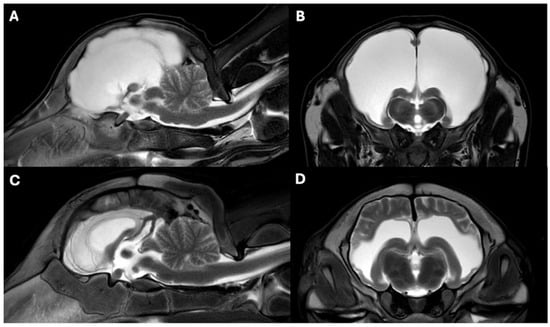

3.3. MRI Findings